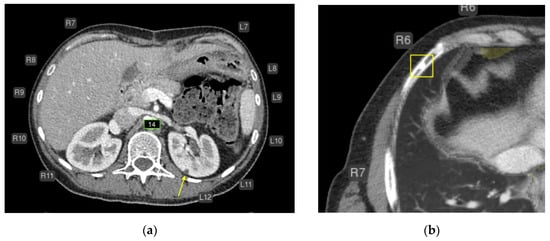

- Urolithiasis (1) (Figure 4).